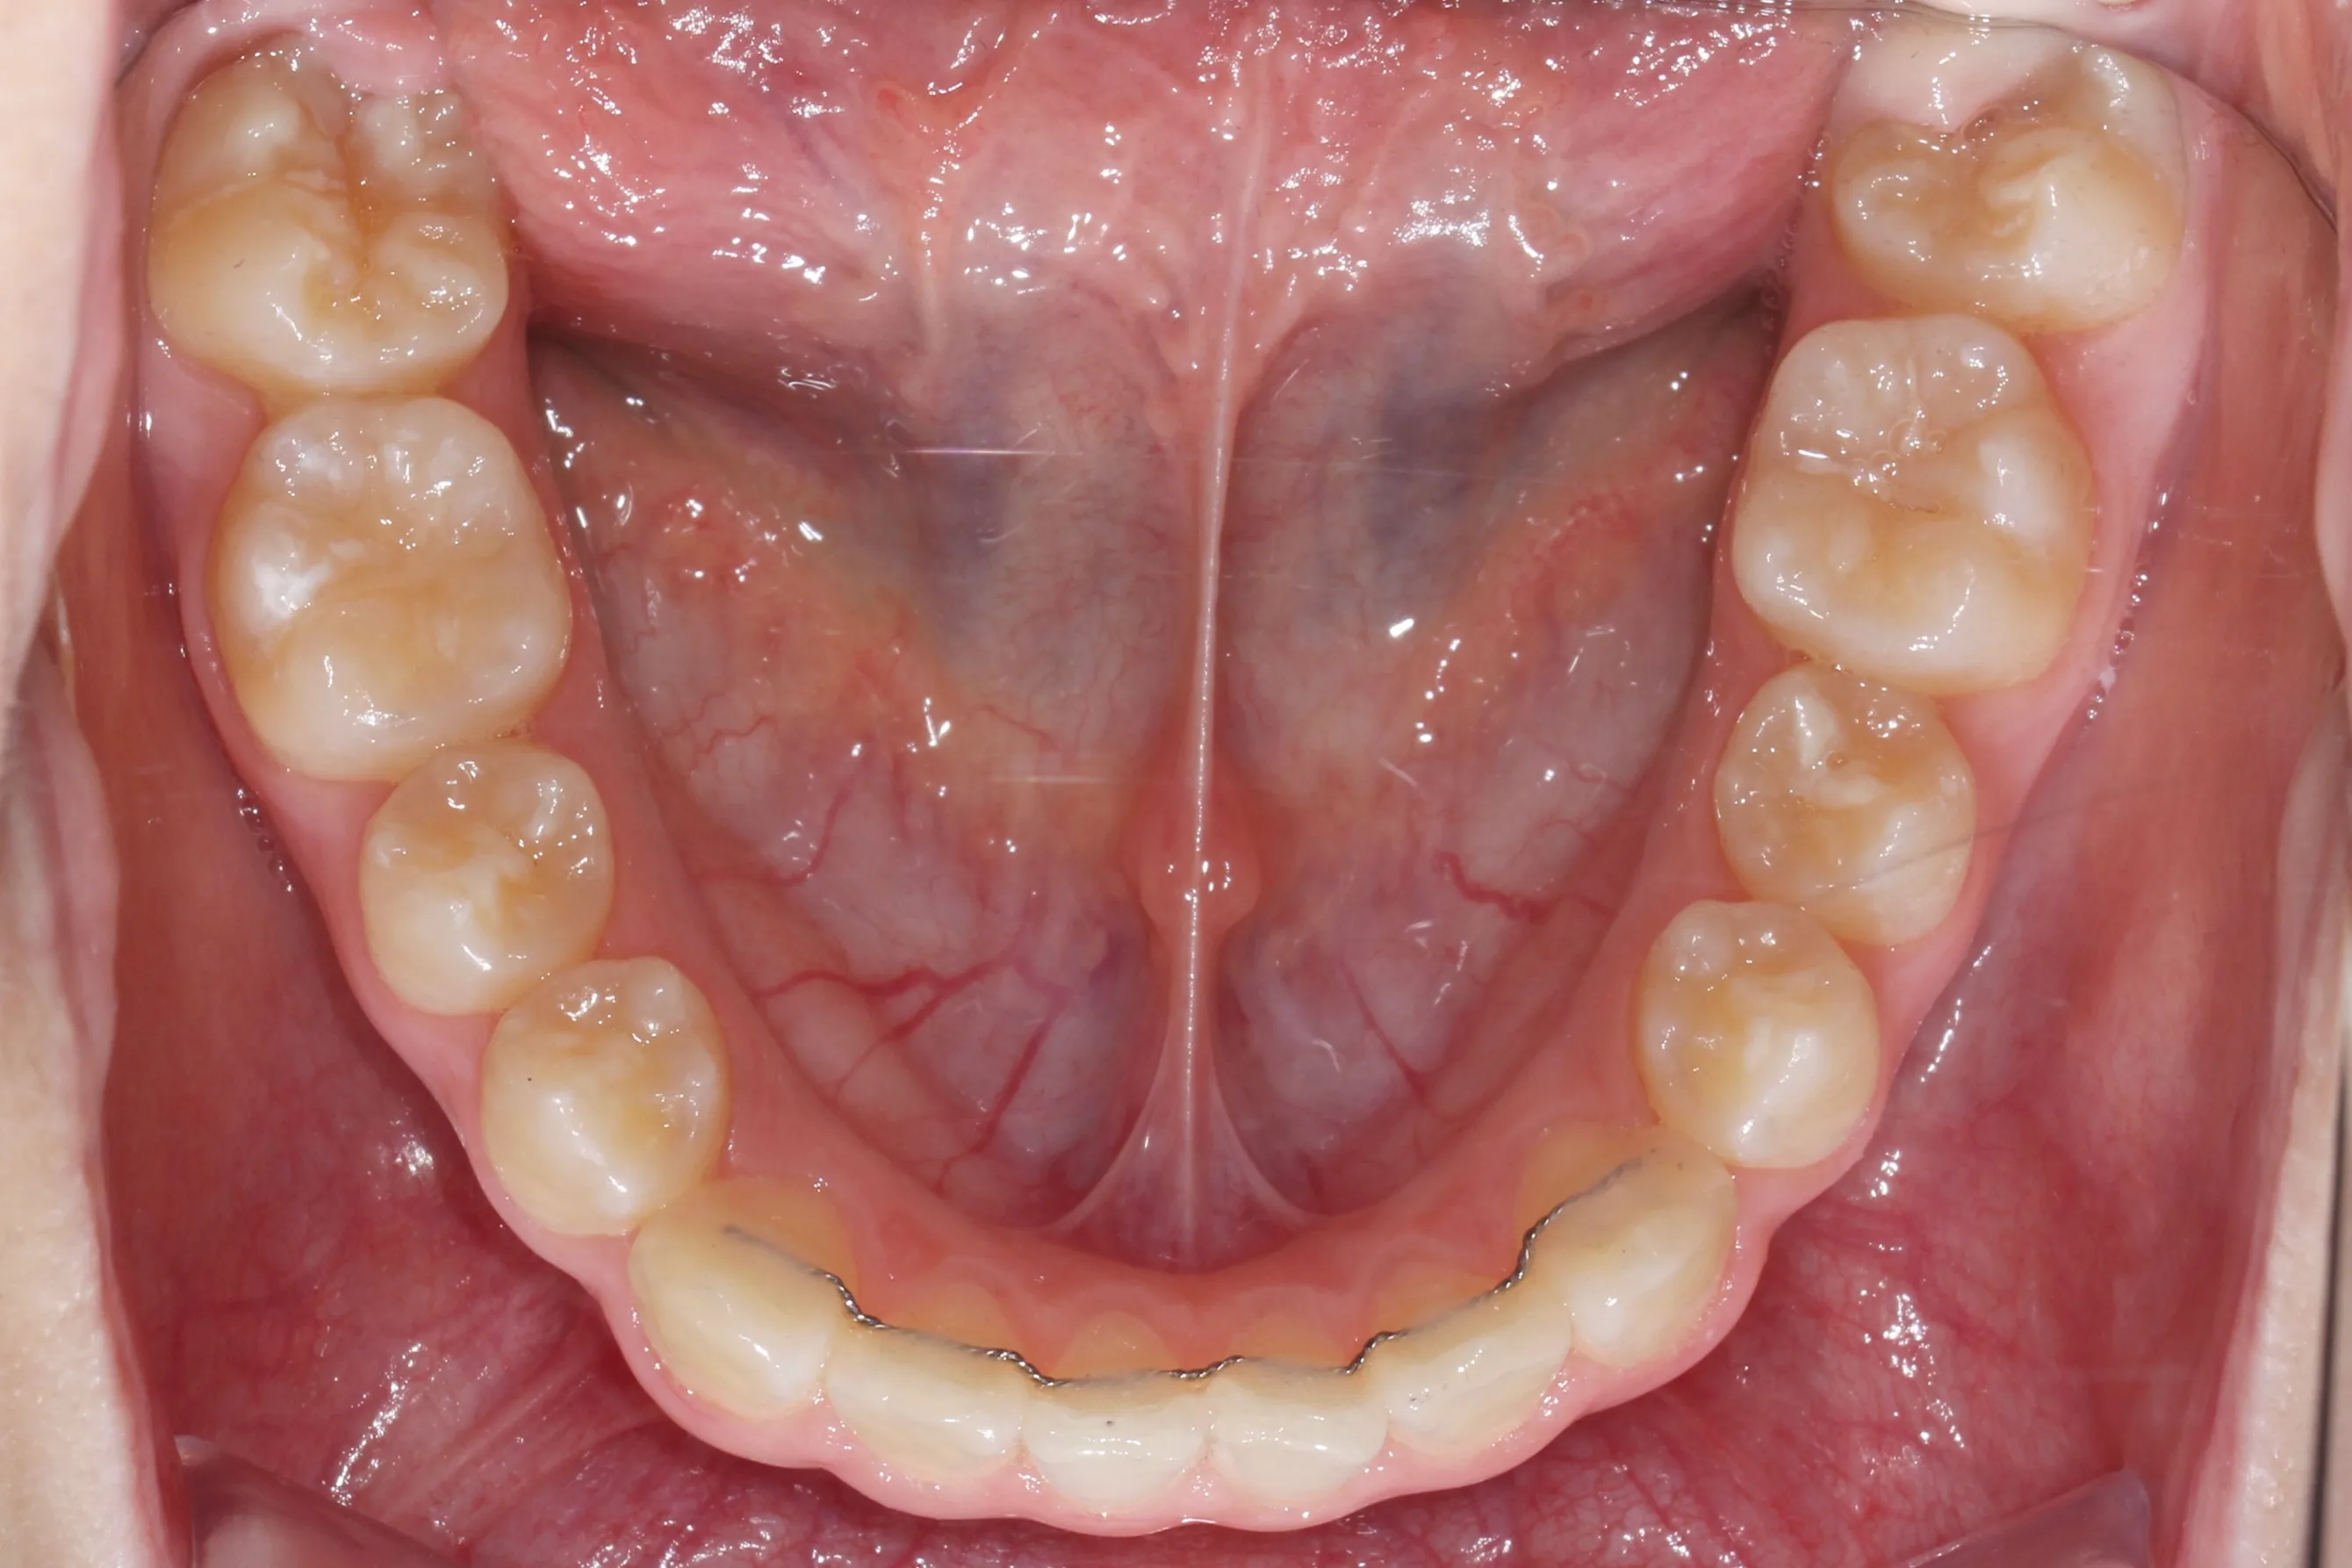

이번 치료에는 인비절라인 퍼스트(Invisalign First)에 하악 전방 견인(Mandibular Advancement, MA wing)을 추가하여 치료를 진행하였습니다. 성장기라는 시기적 특성을 적극 활용하여 아래턱의 점진적인 성장을 유도하고, 과도한 상악 전치부 돌출을 개선하는 데 치료의 핵심 전략을 두었습니다.

2년 7개월의 치료 과정을 거치며 환자분의 협조도 덕분에 안모 프로파일과 교합이 안정적으로 개선되었습니다. 성장기라고 해서 무조건 교정이 어려운 것은 아닙니다. 적절한 시기에 맞춤형 장치를 선택한다면 골격적 불균형을 효과적으로 바로잡을 수 있습니다.